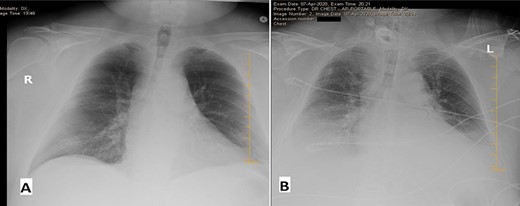

The chest X-ray (Fig. 1A) showed minimal blunting of the left costophrenic angle.

Chest X-ray (CXR) on the day of admission (A) versus Day 3 of admission (B). Initially relatively unremarkable except for minimal blunting of the left costophrenic angle. On Day 3—obtained due to increased PEEP—CXR revealed new bibasilar lung opacities suspicious for COVID-19 pneumonia.

On Day 1 after admission, the initial COVID-19 high-sensitivity PCR nasopharyngeal swab came back as negative. However, postoperatively, high positive end expiratory pressure of 14 mmHg on mechanical ventilation was noted, and this combined with his repeat CXR (Fig. 1B) was suspicious of COVID-19 infection. This prompted a repeat test, which on Day 2 was COVID-19 high-sensitivity PCR positive.